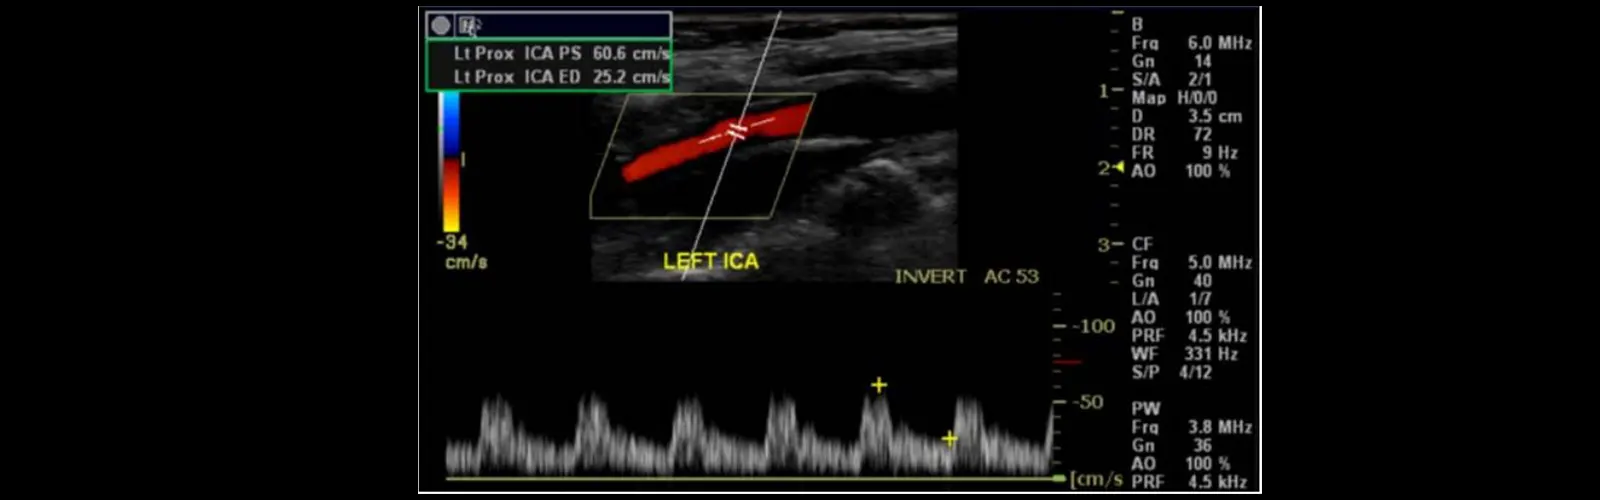

Carotid Color Doppler Ultrasound is a non-invasive diagnostic imaging test that is used to evaluate the blood flow in the carotid arteries, which are the main arteries that supply blood to the brain. During the exam, a handheld device called a transducer is placed on the skin of the neck and moved over the carotid arteries. The probe sends high-frequency sound waves into the body, which bounce off the arteries and create echoes. These echoes are detected by the transducer and used to create images of the carotid arteries and the blood flow within them.

Color Doppler imaging is then used to evaluate the direction and speed of blood flow within the carotid arteries. This information can help to identify any narrowing or blockages in the arteries that can increase the risk of stroke or transient ischemic attack (TIA). The exam can also detect the presence of plaques or other abnormalities in the arterial wall.